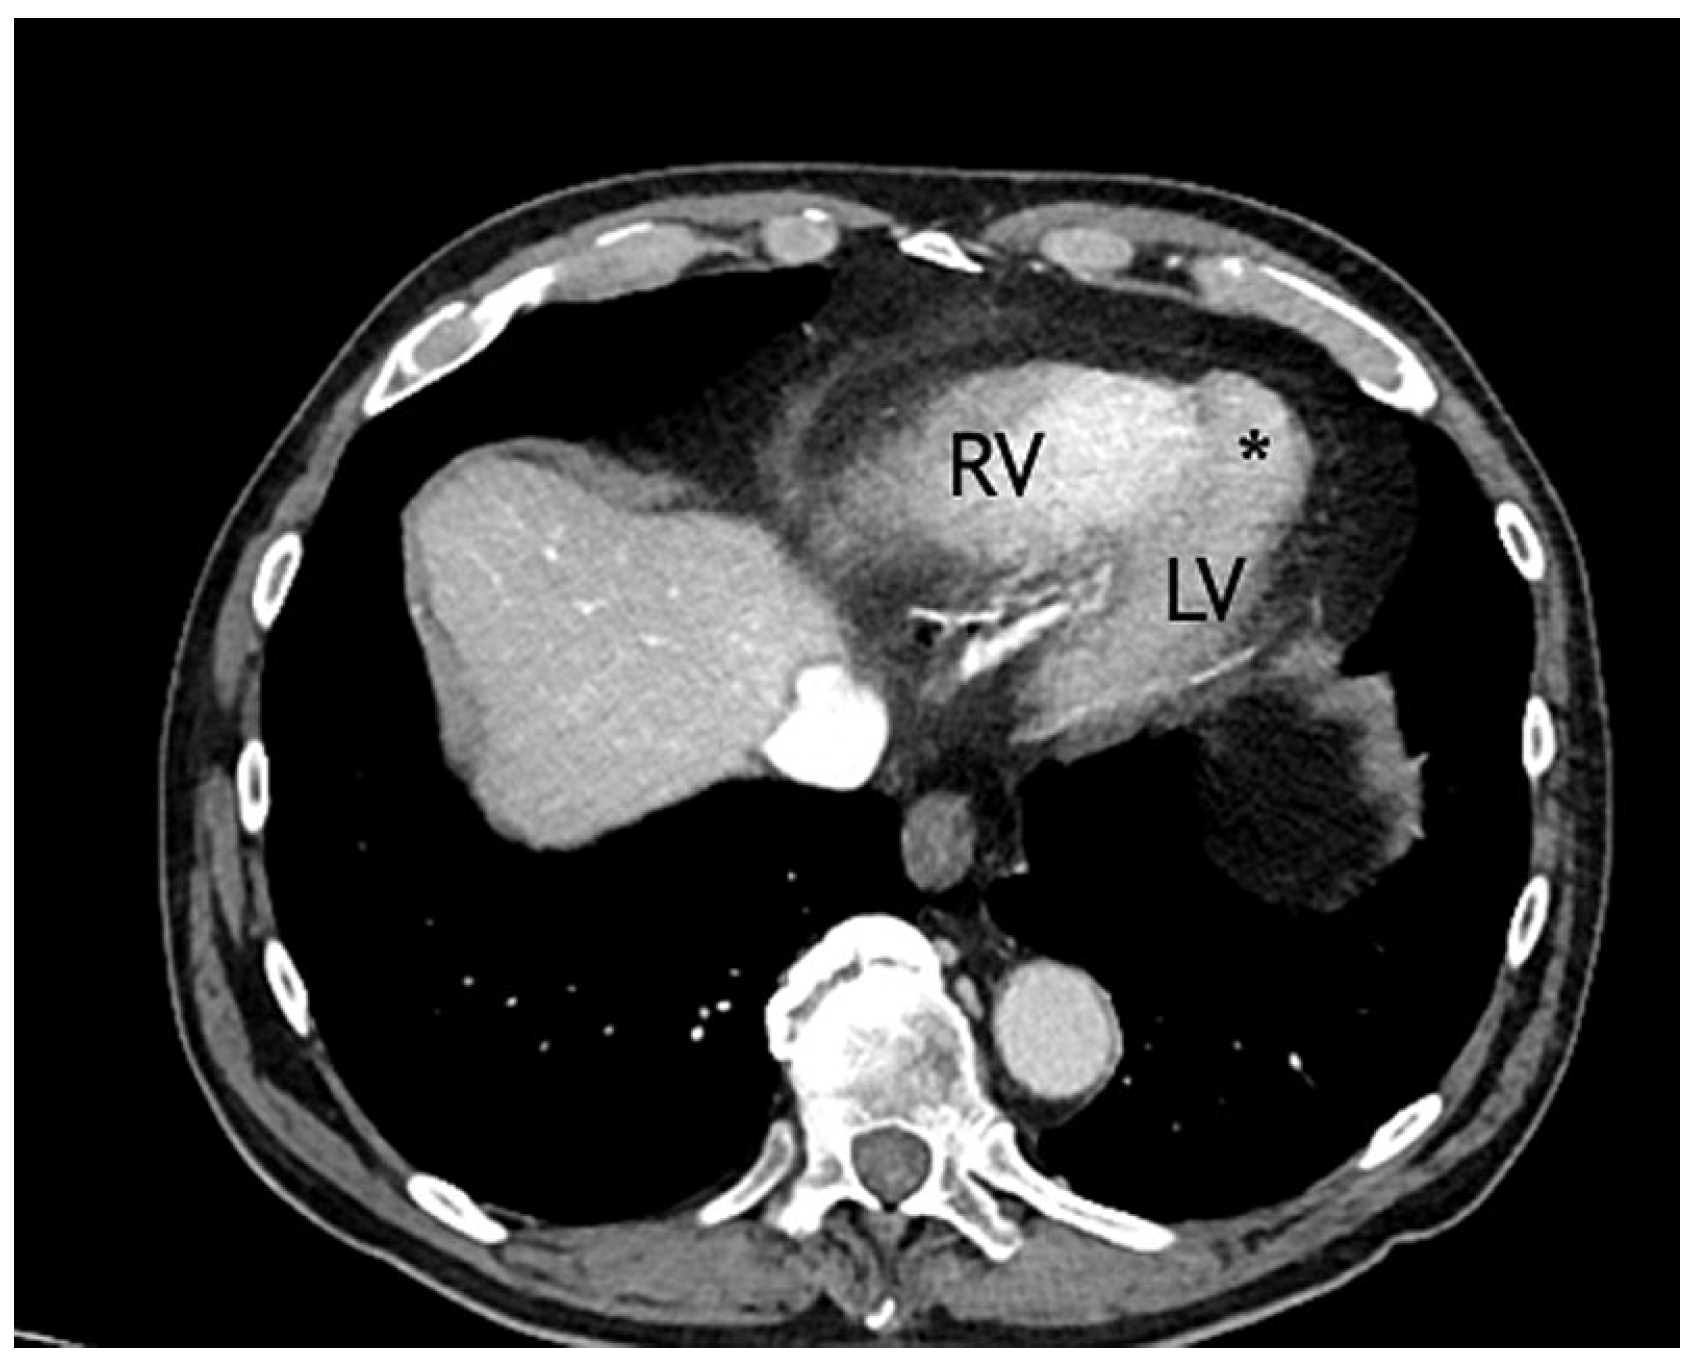

A 79-year-old male, with known ischaemic heart disease, was admitted to our emergency department because of acute abdominal pain and clinical suspicion of a ruptured abdominal aortic aneurism, which was confirmed by a computed tomography (CT) scan. His past history included hypercholesterolaemia treated with statins and silent myocardial ischaemia that was documented on prior myocardial scintigraphy. Emergent endovascular treatment of the aneurysm was successfully performed. The CT scan showed as an incidental finding the presence of a small left apical aneurysm (17 mm in its long axis and 7 mm at the base) (Figure 1).

Figure 1. Thorax computed tomography. * = aneurysmal cavity; LV = left ventricle; RV = right ventricle.